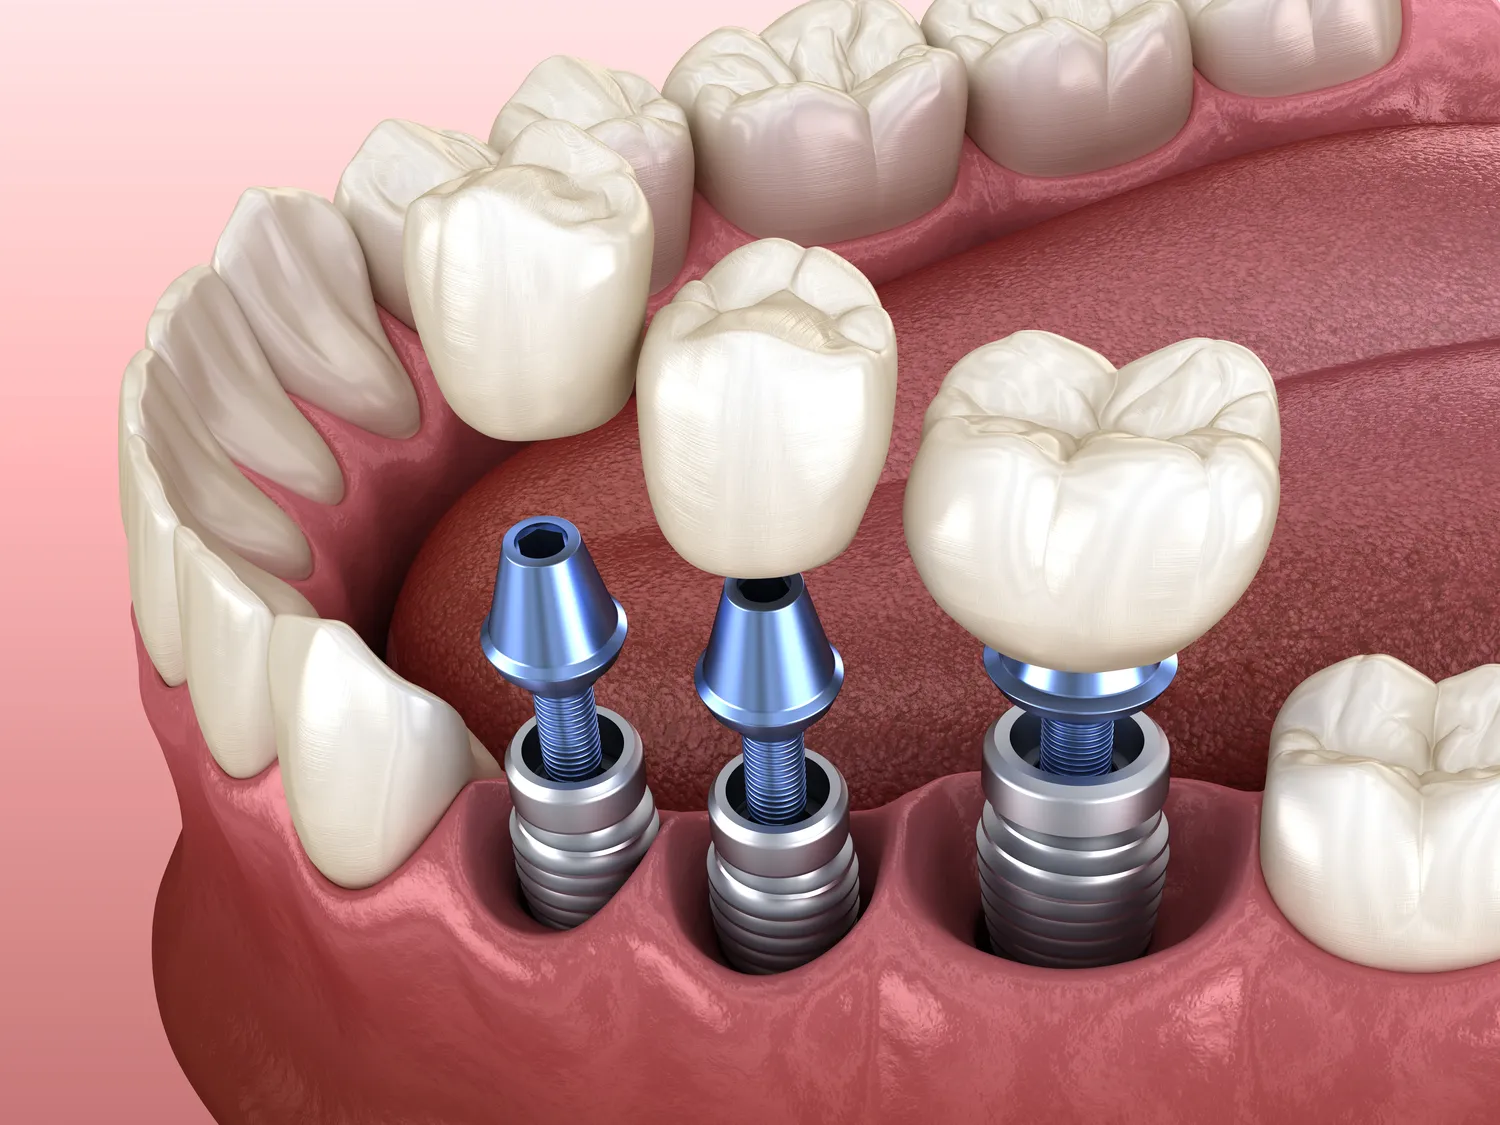

Kolejnym etapem jest przygotowanie miejsca pod implant. W zależności od sytuacji klinicznej, może to obejmować zabiegi augmentacji kości (sterowana regeneracja kości), podniesienie dna zatoki szczękowej (sinus lift) lub usunięcie pozostałości zębów. Te procedury mają na celu zapewnienie odpowiedniej ilości i jakości tkanki kostnej, która będzie stanowić stabilne podparcie dla implantu. Sam zabieg implantacji polega na precyzyjnym umieszczeniu tytanowego wszczepu w kości szczęki lub żuchwy. Procedura ta jest zazwyczaj wykonywana w znieczuleniu miejscowym, co sprawia, że jest bezbolesna dla pacjenta.

Po wszczepieniu implantu następuje okres osteointegracji, czyli zrastania się implantu z tkanką kostną. Jest to kluczowy etap, który zazwyczaj trwa od kilku tygodni do kilku miesięcy, w zależności od indywidualnych predyspozycji pacjenta i lokalizacji implantu. W tym czasie implant staje się integralną częścią kości, zapewniając solidne i trwałe oparcie dla przyszłej odbudowy protetycznej. Po zakończeniu osteointegracji, na implancie umieszcza się śrubę gojącą, która kształtuje dziąseł, a następnie po kilku tygodniach przykręca się lub cementuje na nim koronę protetyczną. Cały proces wymaga cierpliwości, ale efekt końcowy w postaci przywróconego uzębienia jest tego warty.